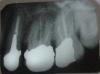

Саркози Опубликовано 13 января, 2011 Поделиться Опубликовано 13 января, 2011 Добрый день,в течение двух примерно лет постоянно имеется свищна десне над 6-ой (с коронкой) вверху слева.Периодически свищ увеличивается, болезненность десны увеличивается, через пару дней все спадает.Предложили: снять коронку, перелечить каналы, поставить новую коронку.Снимет это проблему свища?В последнее время свищ воспаляется чаще, есть ли какие-то способы купировать воспаление самостоятельно?Спасибо. Ссылка на комментарий

juli63 Опубликовано 13 января, 2011 Поделиться Опубликовано 13 января, 2011 Добрый день,в течение двух примерно лет постоянно имеется свищна десне над 6-ой (с коронкой) вверху слева.Периодически свищ увеличивается, болезненность десны увеличивается, через пару дней все спадает.Предложили: снять коронку, перелечить каналы, поставить новую коронку.Снимет это проблему свища?В последнее время свищ воспаляется чаще, есть ли какие-то способы купировать воспаление самостоятельно?Спасибо. как правило, свищ говорит о наличие инфекции в корневом канале.конкретно в вашем случае перелечивание просто необходимо и проблема должна решиться! самостоятельно вы проблему не устраните! Ссылка на комментарий

DokDent Опубликовано 15 января, 2011 Поделиться Опубликовано 15 января, 2011 а все-таки, на время воспаление чем снизить?Саркози,противовоспалительные препараты не решат Вашу проблему.через свищ происходит отток экссудата из околокорневой зоны проблемного зуба,который Вы глотаете.Поэтому не затягивайте визит к доктору.Не стОит без надобности травить себя антибиотиками.Вам правильно сказали-проблему надо решать радикально Ссылка на комментарий